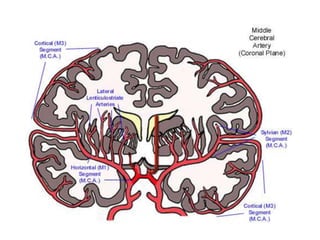

MCA syndrome

MCA is the second of the two main branches of the

internal carotid artery.

Supplies:

• Lateral aspect of cerebral hemisphere( frontal,

temporal, and parietal lobes )

• Subcortical structures (IC, corona radiata , globus

pallidus, putamen )

MCA syndrome MCA isthe second of the two main branches of the internal carotid artery. Supplies: • Lateral aspect of cerebral hemisphere( frontal, temporal, and parietal lobes ) • Subcortical structures (IC, corona radiata , globus pallidus, putamen )

Signs and symptoms: • • • • • • Contralateralhemiparesis (UL and face > LL) Contralateral sensory loss (UL and face > LL) Motor speech impairment Receptive speech impairement Global aphasia Perceptual deficits (unilateral neglect, anosognosia, apraxia and spatial disorganization) • Contralateral homonymous hemianopsia • Sensory ataxia Structures involved : Primary motor area, primary sensory area, broca’s area, Wernicke’s area, optic radiation in internal capsule